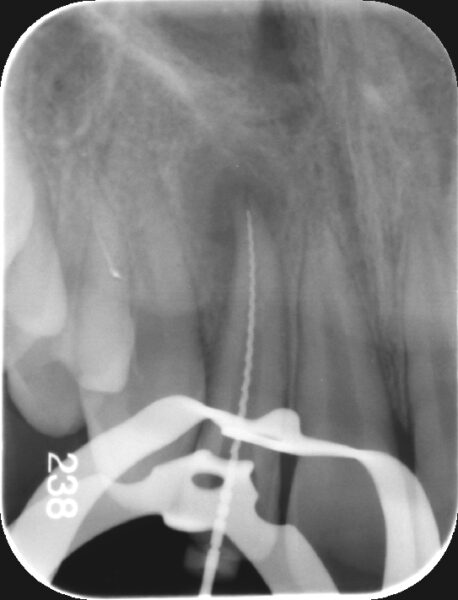

【術前レントゲン】

根の先端に骨欠損(黒くなっている部分)が認められます。また、根の先端が完全には出来上がっていない根未完成の状態です。

【術中マイクロ写真ならびに術中レントゲン写真】

根の先端を確かめるためのレントゲンです。レントゲン上では実際の根の先端より手前側に根の先端があることが確認されます。